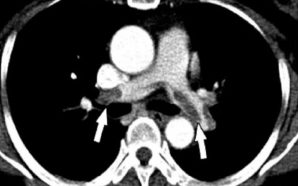

• What is a Pulmonary Embolism?

Pulmonary embolism is a blockage of a pulmonary artery, which is a blood vessel in the lung. Pulmonary arteries bring deoxygenated blood from the right side of the heart to the lungs, and this allows oxygen to be absorbed by the blood. Given the role of these arteries, pulmonary...